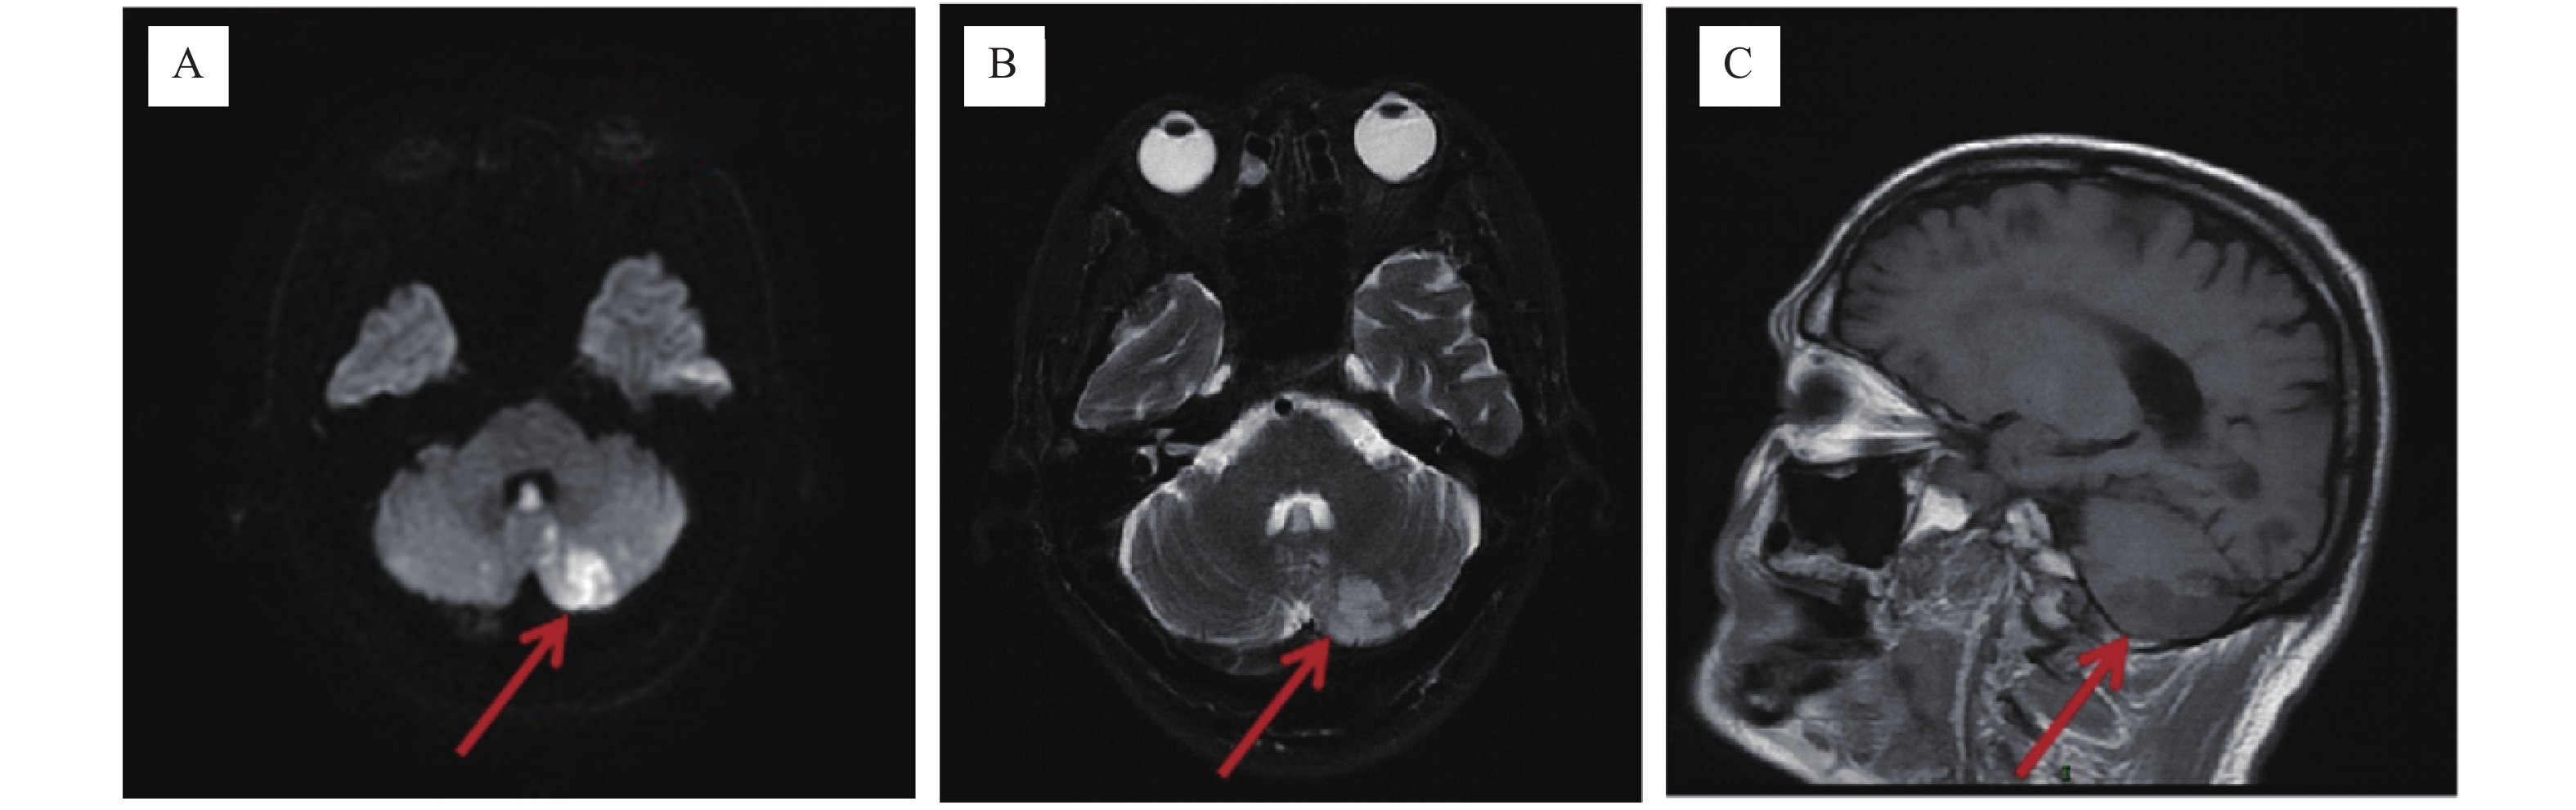

miR-132、BDNF和NRG-1在急性缺血性脑卒中相关血管性痴呆诊断及预后中的应用研究

刘塞兵, 闫立萍, 孙阿妮

摘要(233) HTML(229) PDF (85)

摘要:

目的  探讨血清微小RNA-132(microRNA-132,miR-132)联合脑源性神经营养因子(brain-derived neurotrophic factor,BDNF)、神经调节蛋白-1(neuroregulatory protein-1,NRG-1)在急性缺血性脑卒中(acute ischemic stroke,AIS)相关血管性痴呆(vascular dementia,VD)诊断及预后评估中的应用。  方法  连续纳入西安高新医院2022年8月至2025年1月接诊的AIS并发VD患者183例为VD组,对其随访6个月根据预后情况分为不良组(n = 54)、良好组(n = 129)。另选取同期就诊的未并发VD的AIS患者175例为非VD组。分析AIS并发VD患者预后不良的影响因素及血清miR-132、BDNF、NRG-1水平预测AIS并发VD患者预后不良的效能。  结果  VD组血清miR-132、BDNF水平均低于非VD组(P < 0.05)。血清miR-132、BDNF、NRG-1是AIS并发VD的影响因素(P < 0.05)。三者联合诊断AIS并发VD的AUC(0.860)高于单独诊断的AUC(0.796、0.758、0.713)(P < 0.05)。与良好组相比,不良组入院MMSE评分≤20分占比较高,血清miR-132、BDNF、NRG-1水平降低(P < 0.05)。血清miR-132、BDNF、NRG-1是AIS并发VD患者预后的影响因素(P < 0.05)。联合预测AIS并发VD患者预后的曲线下面积(AUC)(0.920)显著高于各指标单独预测的AUC(0.806、0.788、0.850)。  结论  AIS并发VD患者血清miR-132、BDNF、NRG-1水平均降低,三者联合检测在AIS相关VD诊断及预后评估中可能具有一定的应用价值。